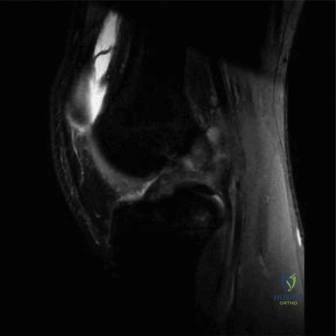

Figures 11a and 11b show the T2-weighted MRI scans of the lumbar spine of a 53-year-old woman who has low back and right lower extremity pain. What structure is the arrow pointing to in Figure 11a?

Explanation